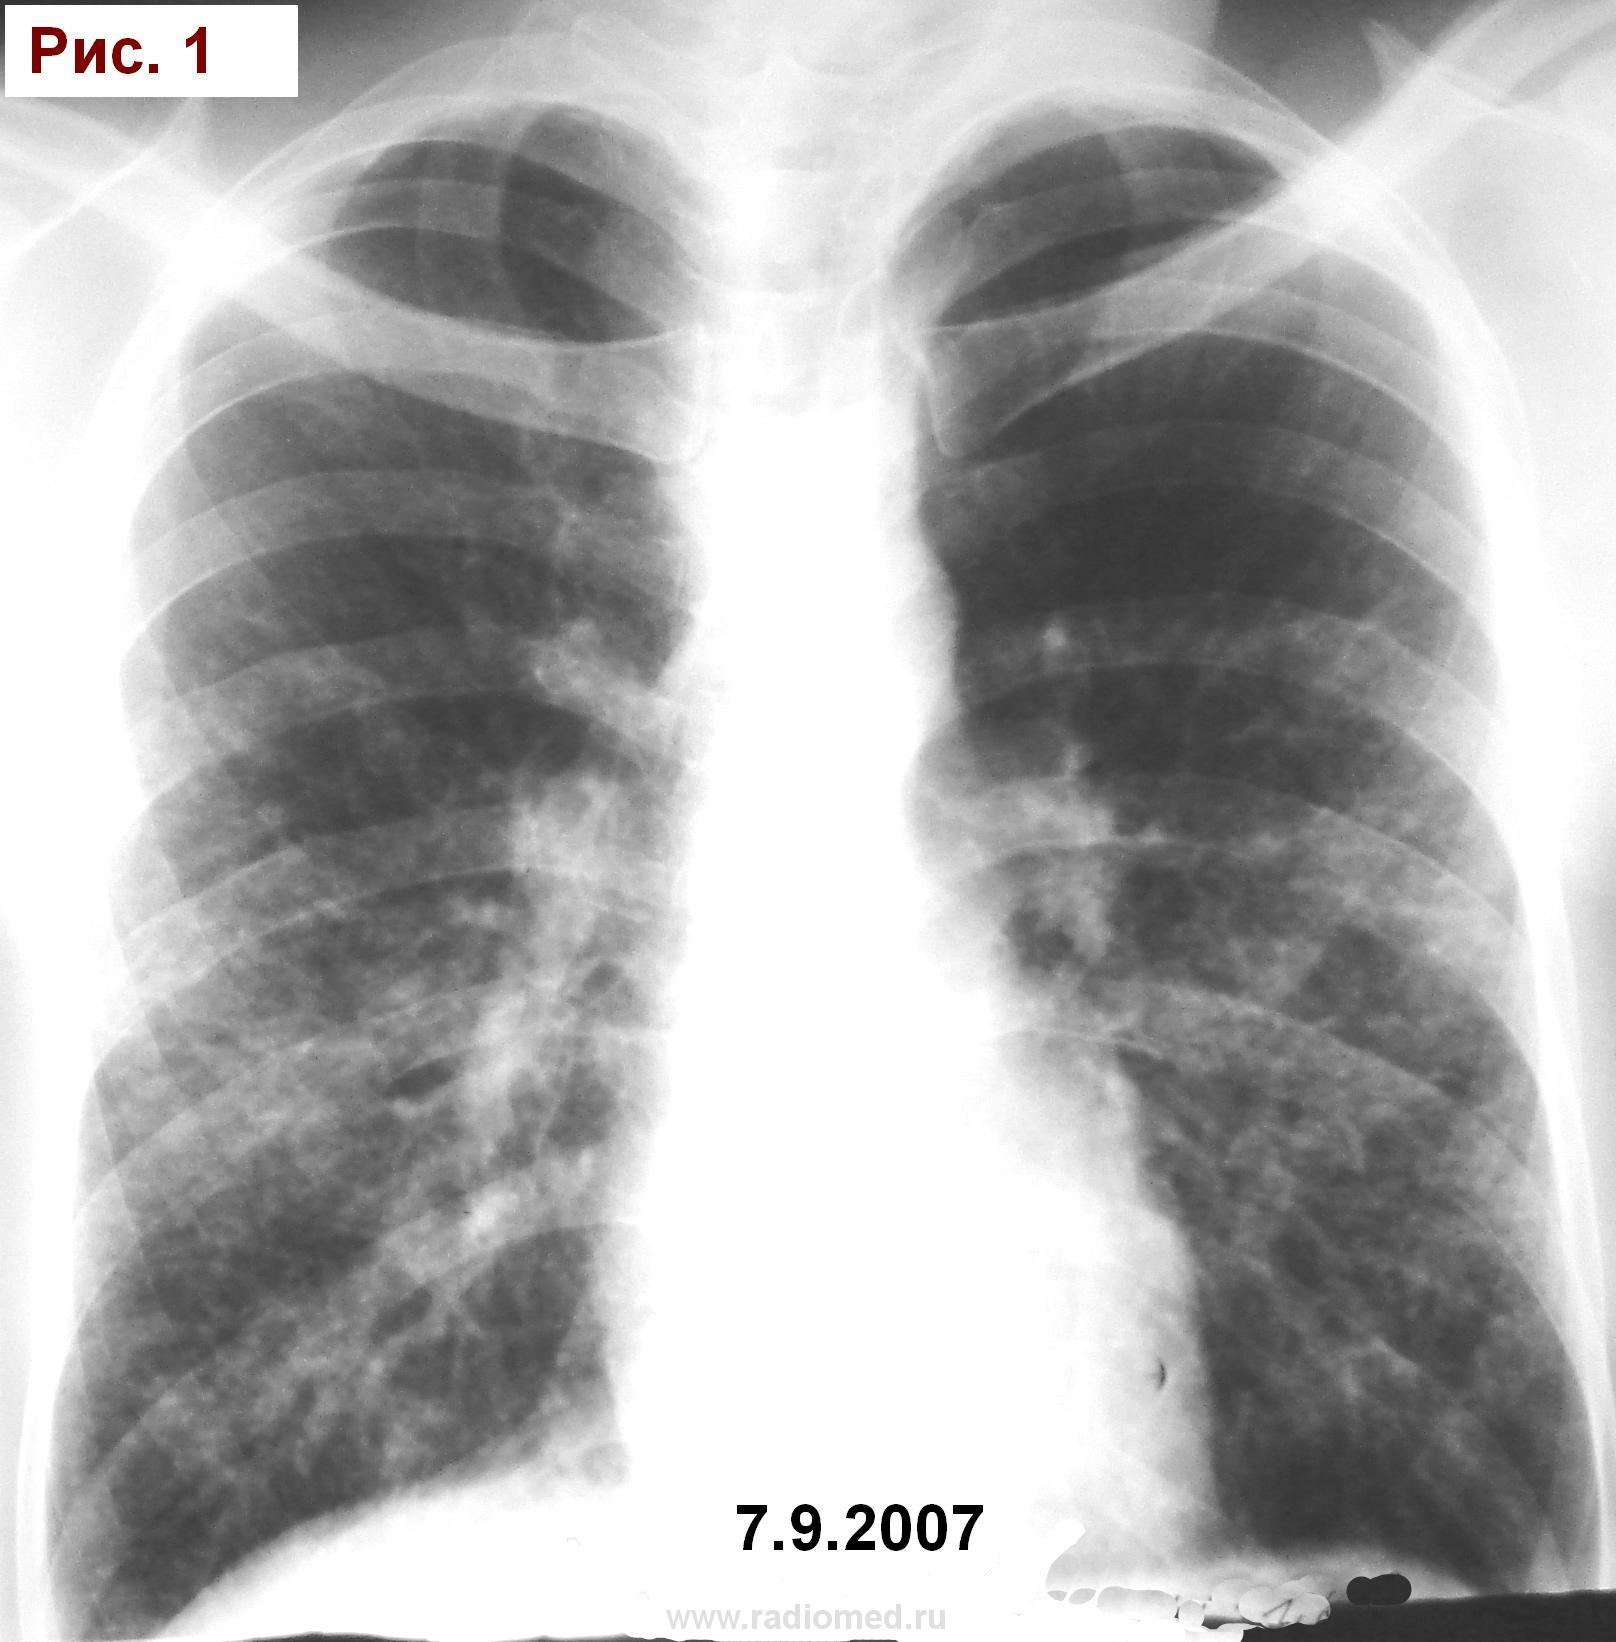

Муж.1974 г. р. Изменения впервые выявлены при проверочной флюорографии 2007 (Рис.1). Выполнена  КТ  легких (См фрагмент. Рис.2). Исчез. Продолжал работать. Не лечился. Пришел на обследование в 11.2011г. с жалобами на покашливание. Температура, кровь: норма. (Рис.3).  О какой патологии  легких можно думать? Я предположил саркоидоз. Специалистов по КТ очень прошу разъяснить рисунок 2. С уважением Nik.

По имеющимся картинкам предположила бы саркоидоз, но помимо ретикулярного и узелкового паттерна по фото КТ-плёнки, могут быть и другие изменения на оригинале (dicom-файлы). Диф.ряд тут:

http://www.radiomed.ru/publications/luchevaya-diagnostika-diffuznykh-interstitsialnykh-zabolevanii-legkikh-dizl-obshchie--0